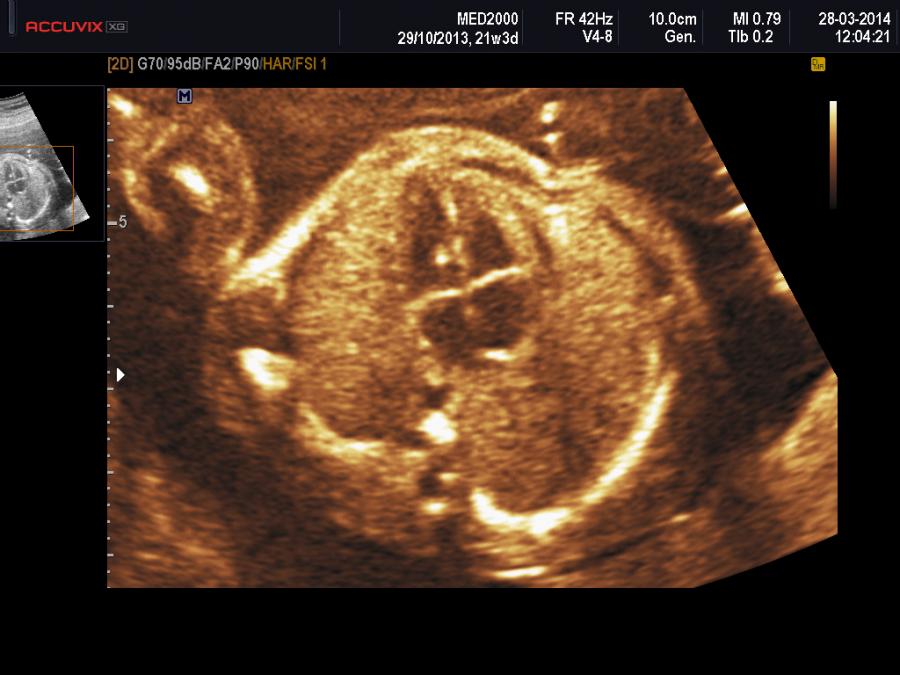

Focus Iperecogeno Ventricolo Sinistro Isolato

Focus Iperecogeno Nel Ventricolo Sinistro Del Cuore Fetale Cos E L Iperfocus Ed E Pericoloso

Focus Iperecogeno Nel Ventricolo Sinistro Del Cuore Fetale Diagnosi Cause

Focalizzazione Iperecogena Nel Ventricolo Sinistro Del Cuore Fetale Diagnosi Cause

Golf Ball O Focus Iperecogeno Del Cuore Del Feto Cos E Tutto Mamma